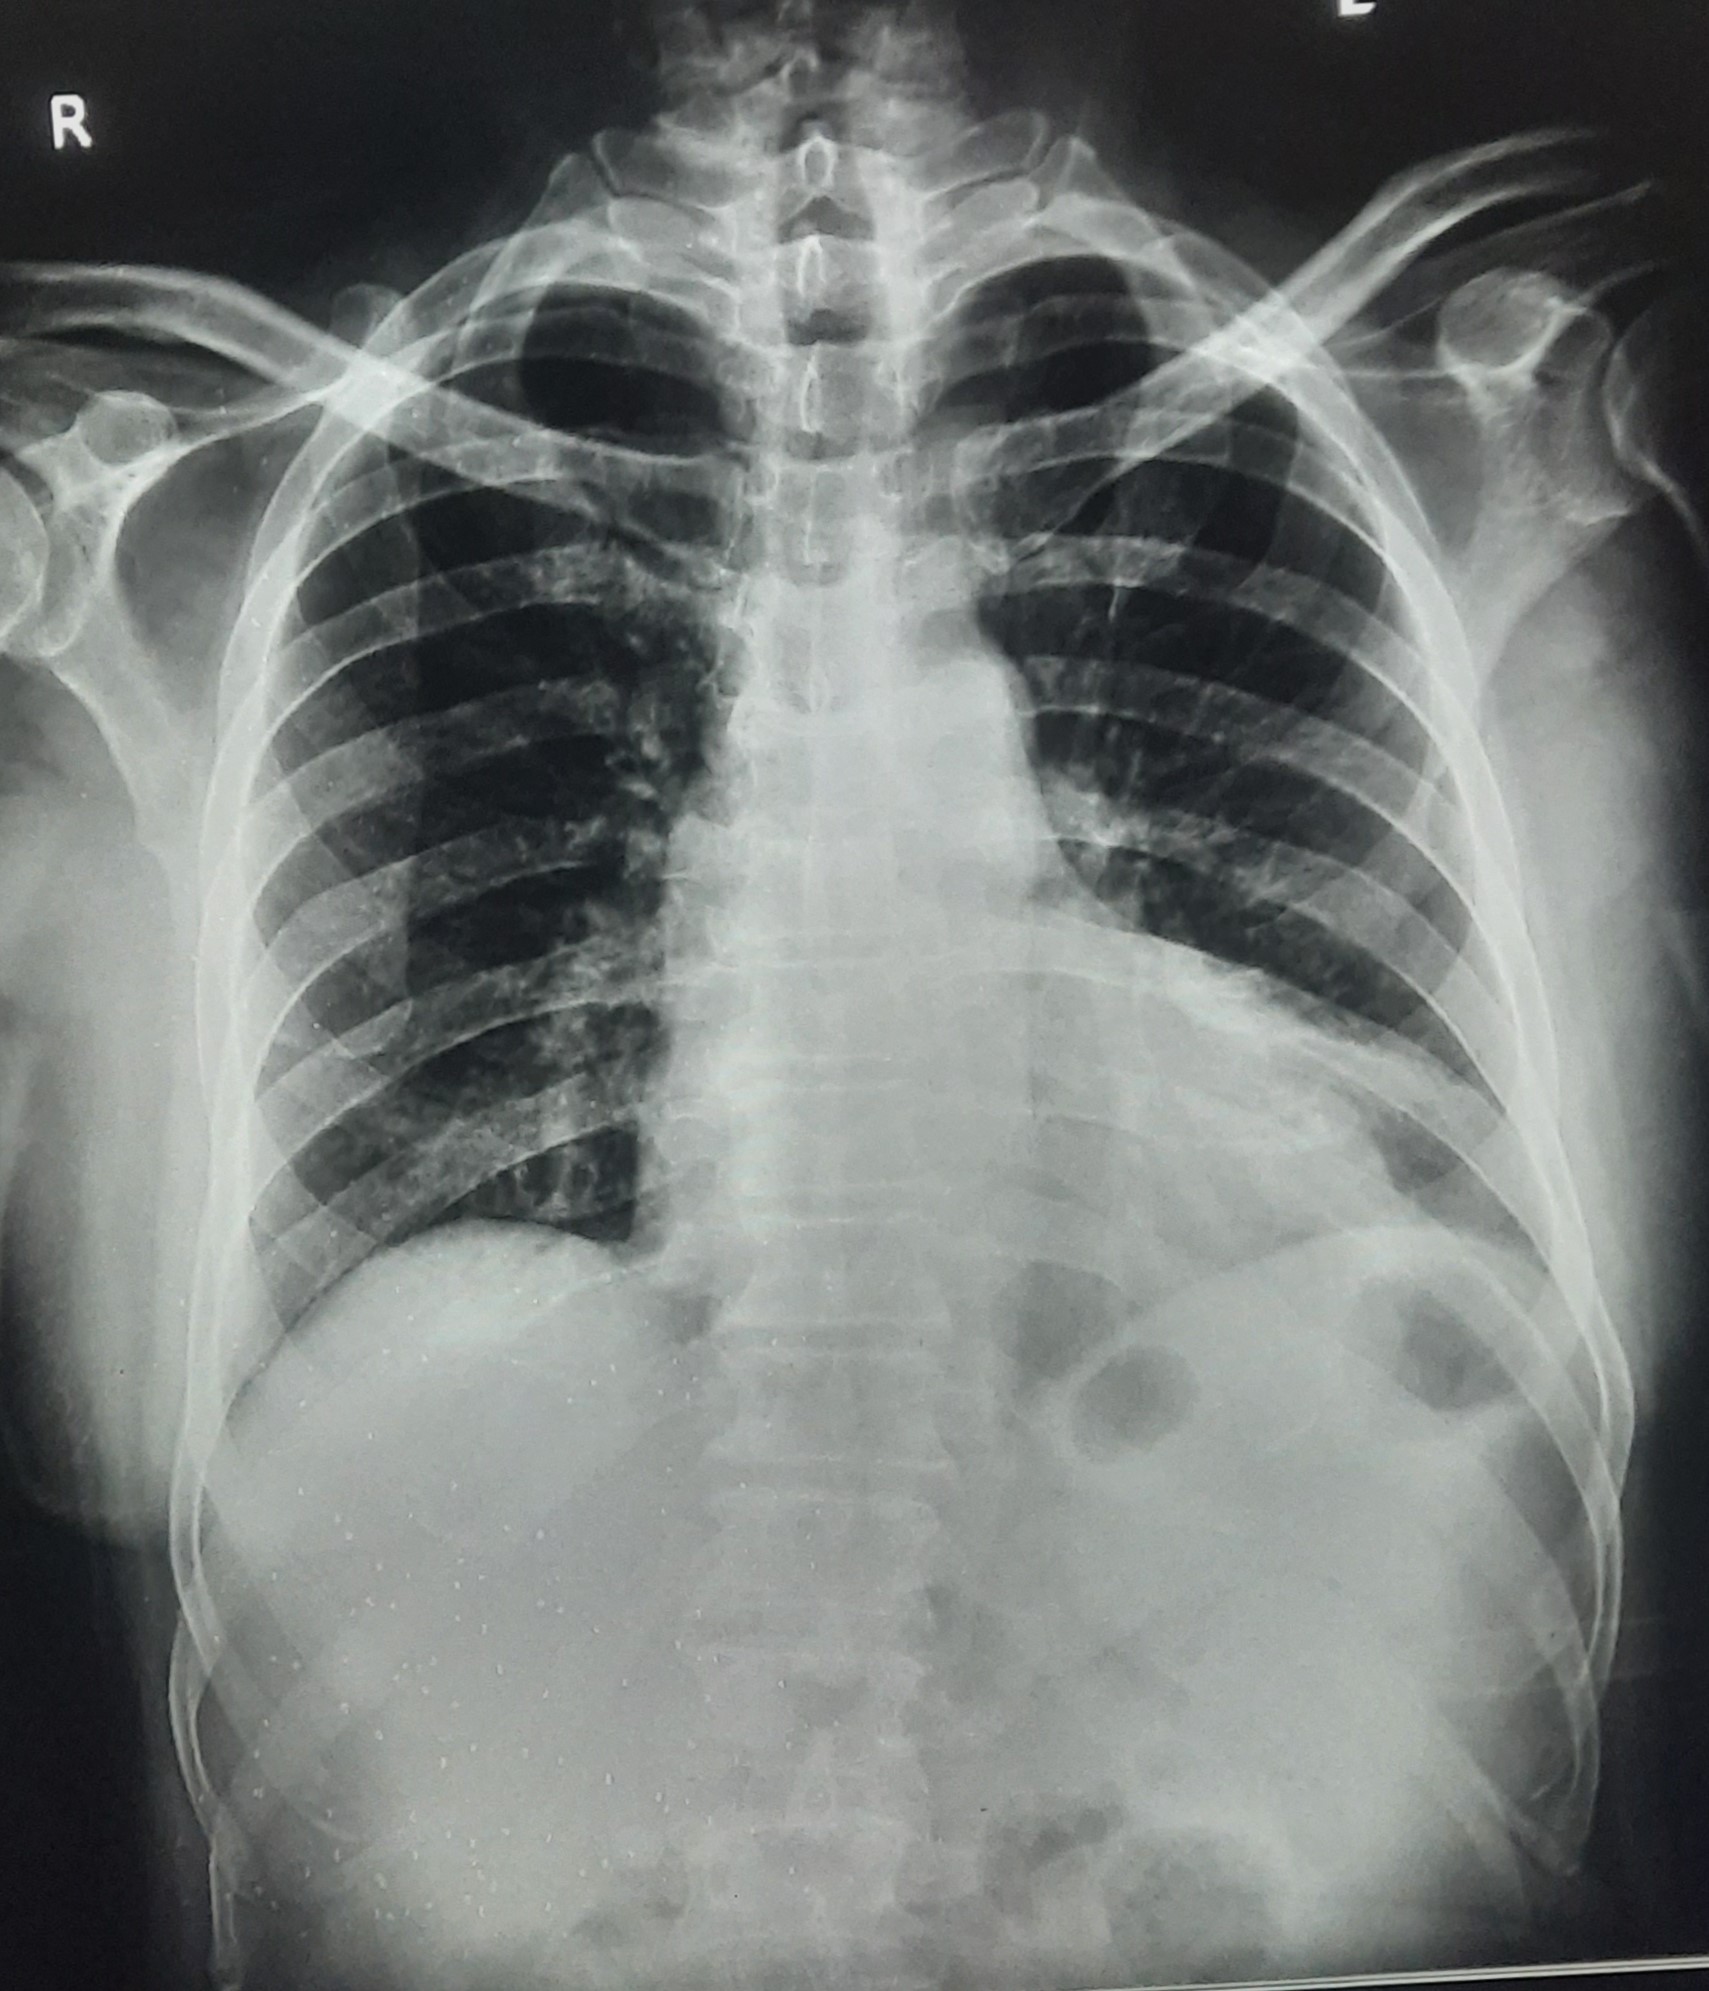

| 318 | IGGMC, Nagpur, Nagpur | P2 | 29-4154 | Tahera Bee | Consent taken on Paper | 70 Yrs. |

Provisional Diag : Post TB Bilateral Bronchiectasis

Final Diag : Post TB sequalae, Bilateral Bronchiectasis In Lower Lobe With Type 1 Respi Failure With Sepsis With Septic Shock With SYST HTN |

Post TB Sequelae | Abnormality visible on x-ray |